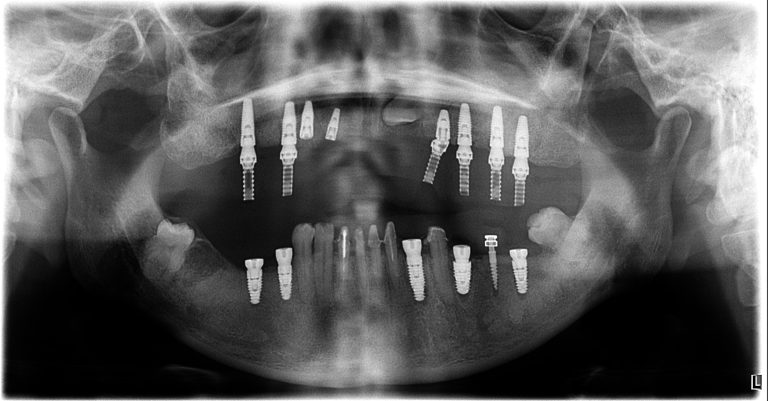

上顎 All on 8,下顎 All on 7

上顎 All on 8